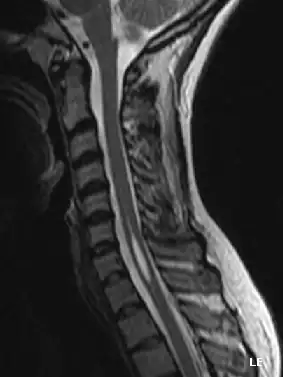

L'imagerie par résonance magnétique est l'examen clef[7]. Il permet de mettre en évidence une cavité oblongue à l’intérieur de la moelle, remplie de liquide cérébrospinal en regard de plusieurs vertèbres. Toutefois son interprétation doit être discutée car la présence de cette cavité pourrait aussi être le vestige d'un canal central non collabé issu de l’embryogenèse. Ainsi il est important de confronter ce résultat à la présence éventuelle d'autres causes pathogéniques : malformation de Chiari, scoliose, distension de moelle spinale, traumatisme de voisinage…